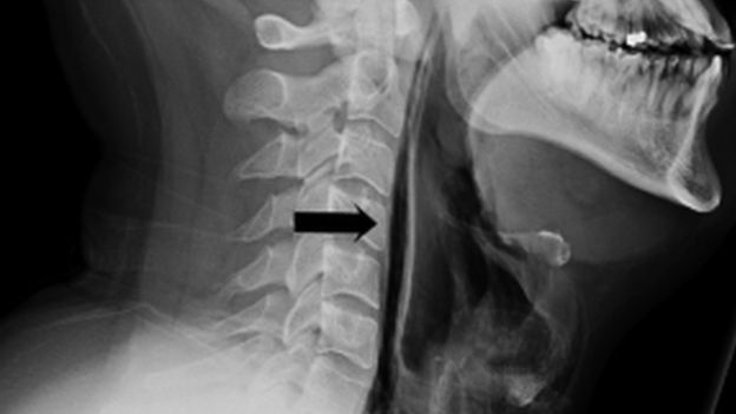

Çekilen röntgen sonucu, nefes borusundan kaçan havanın boğazındaki yumuşak doku ve boyuna gittiği anlaşıldı. Hasta, dokular iyileşene dek yedi gün boyunca bir tüple beslenmek zorunda kaldı ve daha sonra taburcu edildi. Hastanın tedavi edildiği Leiceste’daki hastanenin Kulak Burun Boğaz bölümündeki doktorlar ise, “Burun ve ağzı kapatarak hapşırığı durdurmak tehlikeli bir şey ve kesinlikle yapılmamalı” diyor. (BBC Türkçe)